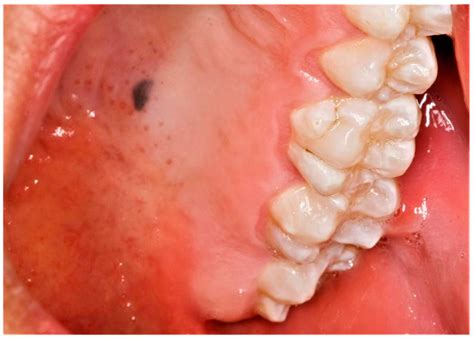

Melanoma oral en el paladar duro. Fuente: Wikipedia

En las fases iniciales, la apariencia es como de un parche pigmentado, con alteración del color y la textura de la mucosa, pero sin otro tipo de sintomatología.

Clínicamente, el MMO se puede presentar como una lesión macular o nodular con superficie de color de grisáceo, pardo o negro-violáceo, pero el color varía en una amplia gama pudiendo incluso presentarse como una lesión despigmentada.

López et al. describen 5 tipos de melanoma intraoral en base al aspecto clínico: melanoma nodular pigmentado, nodular no pigmentado, macular pigmentado, melanoma pigmentado mixto, melanoma no pigmentado mixto. La característica clínica que suele ser común a todos ellos es que la lesión inicial se encuentra rodeada por lesiones satélite.